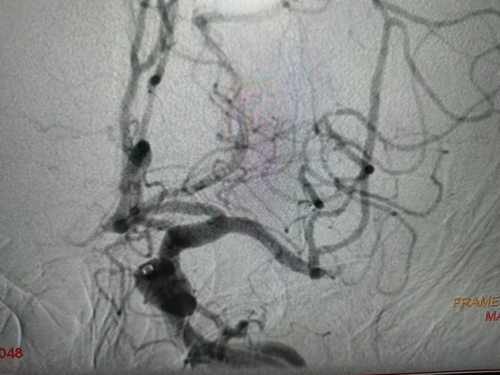

術前

術后

時間就是健康,時間就是速度。他們迅速評估患者病情,經家屬同意,患者被緊急送往急診介入手術室,進行閉塞血管開通并藥物球囊形成術。術中,股動脈穿刺、置導管鞘、入導絲、送入球囊、加壓擴張,操作流程嚴謹、規(guī)范、順暢,整個過程一氣呵成。僅用時15分鐘,閉塞血管順利開通。術后,患者無明顯不適,持續(xù)觀察穿刺部位無滲血,足背動脈搏動良好,腦梗癥狀改善。